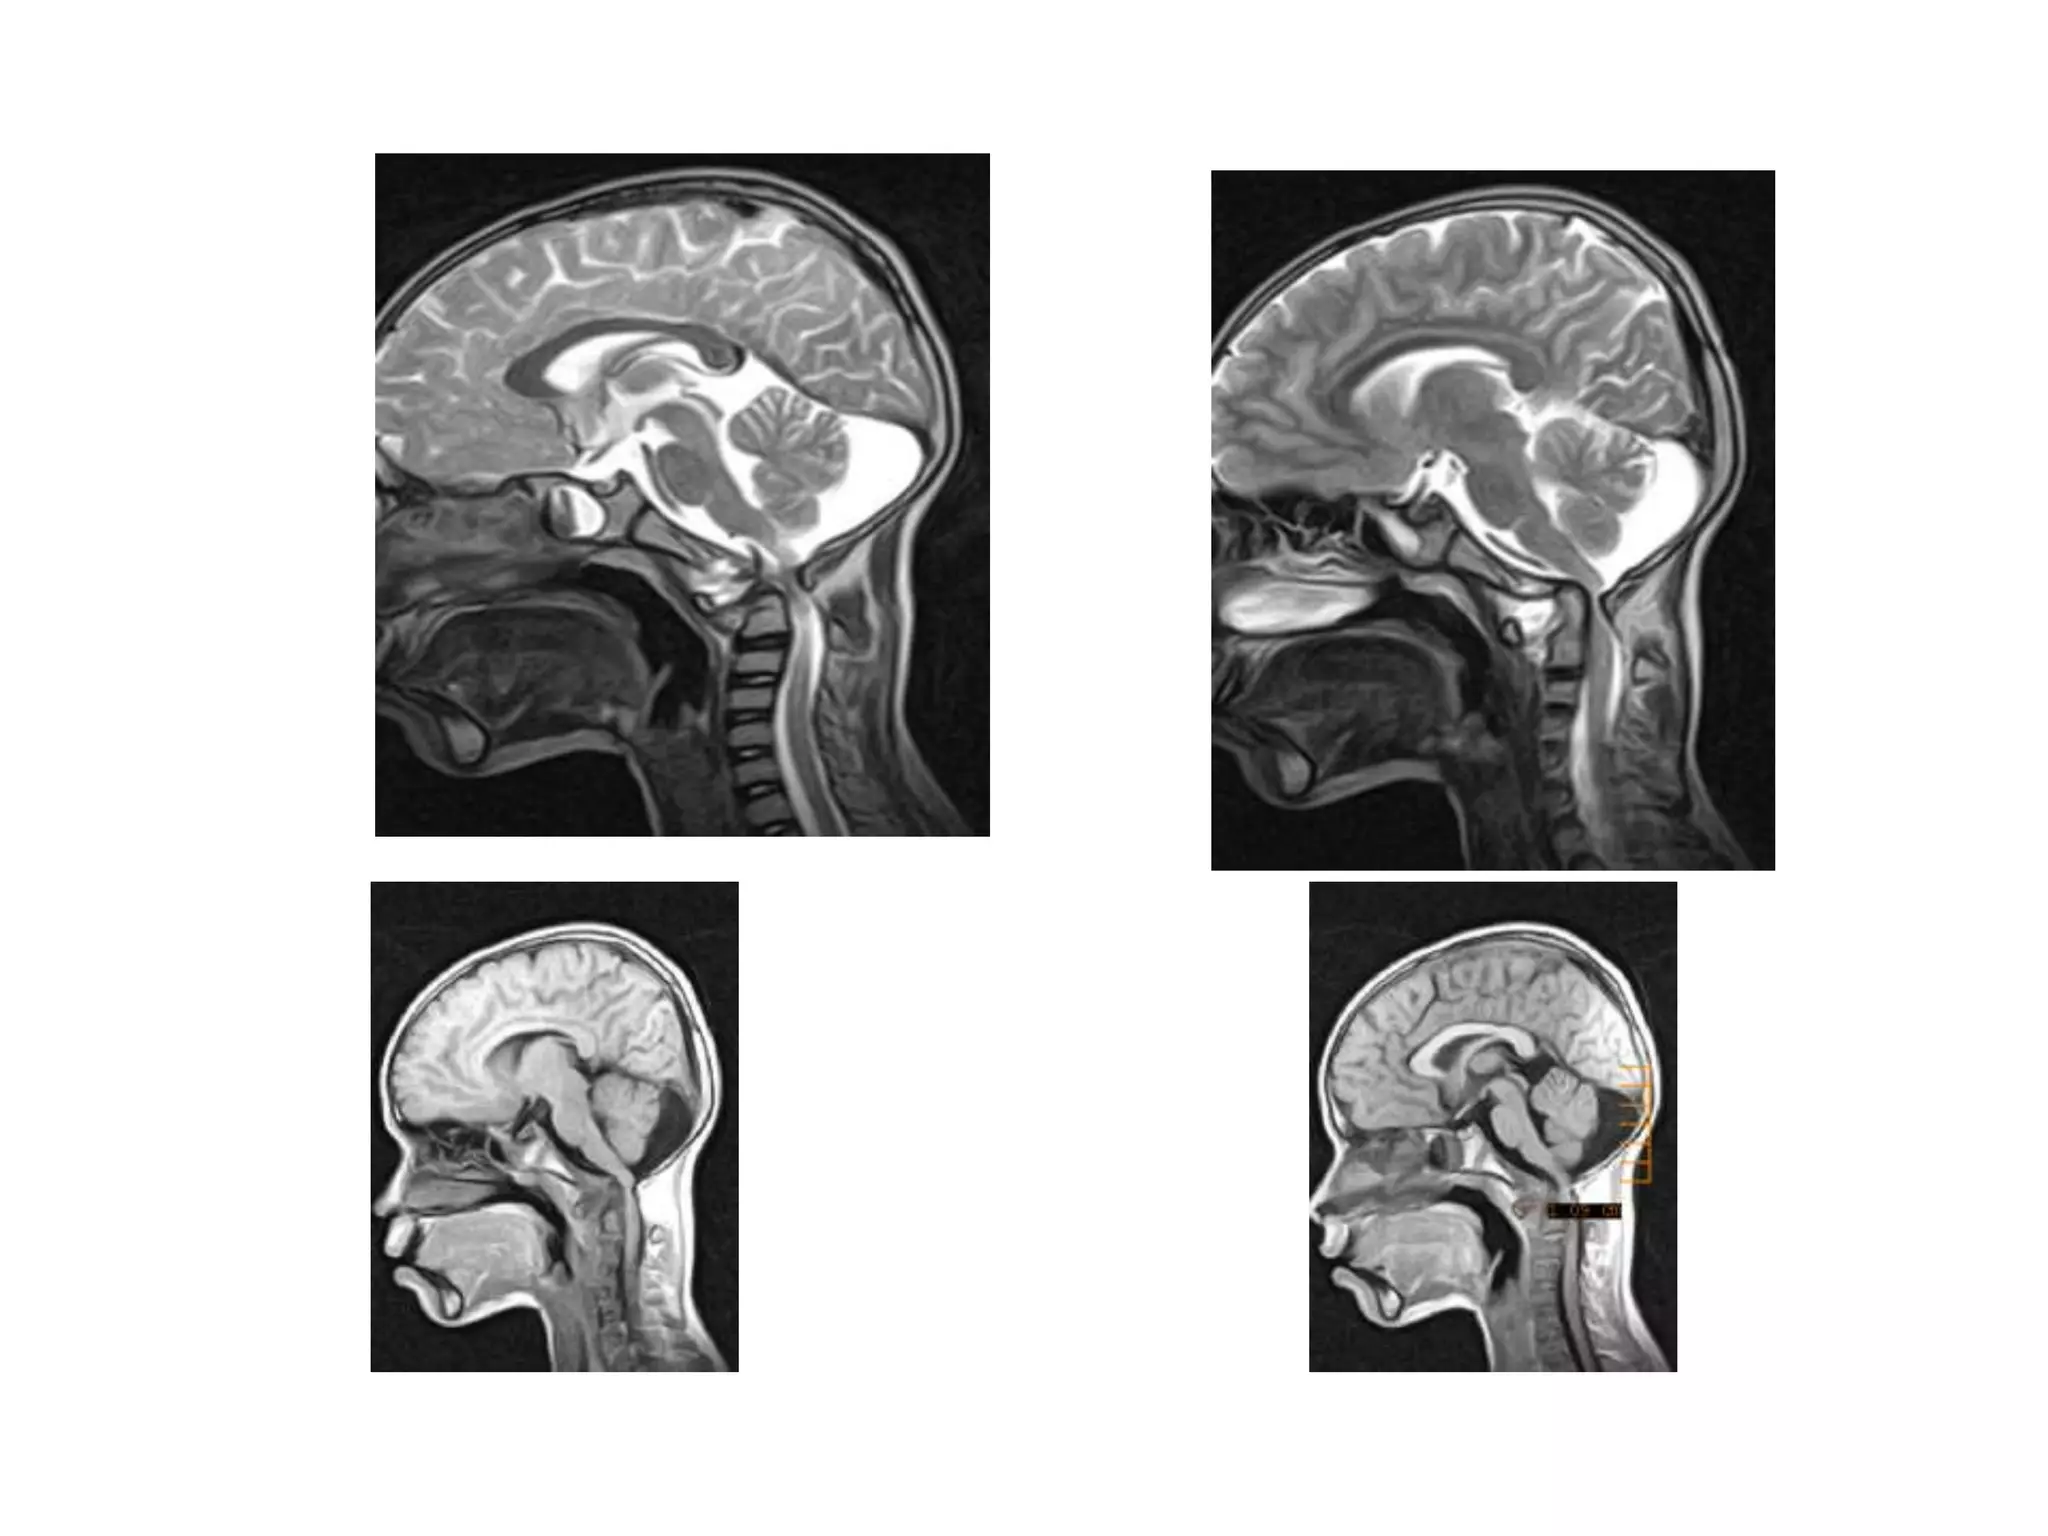

KINEMATIC MRI IN BI